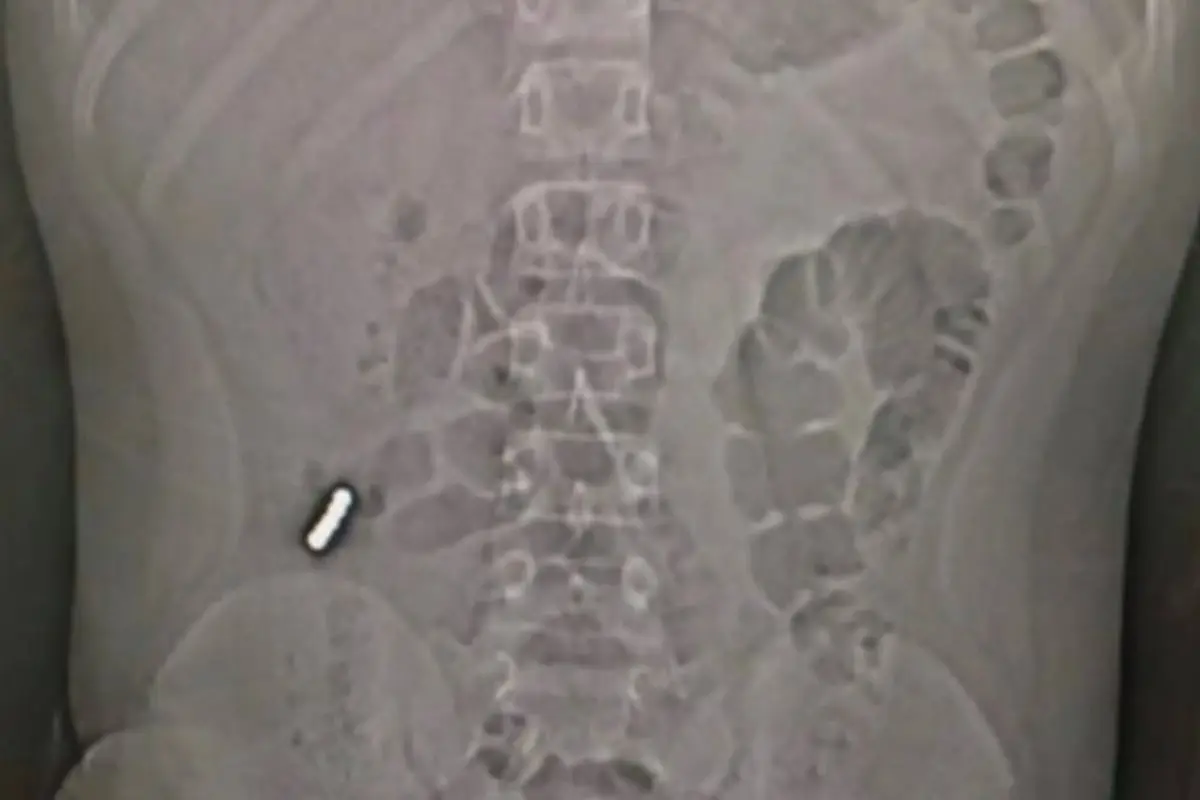

Quien publicó un ejemplo bastante gráfico, al compartir una radiografía de un menor que tragó un imán, fue el doctor Sebastián Ugarte.

"Un menor de once años tras intensos dolores abdominales debió ser operado por culpa del 'Challange de RRSS de ingerir imanes', esto puede producir obstrucción intestinal, lesiones por isquemia de la mucosa y submucosa, perforaciones y peritonitis", explicó el profesional.

Luego puntualizó que "ya son 7 menores operados en Chile. El padre del menor desea informar y advertir a otros padres".